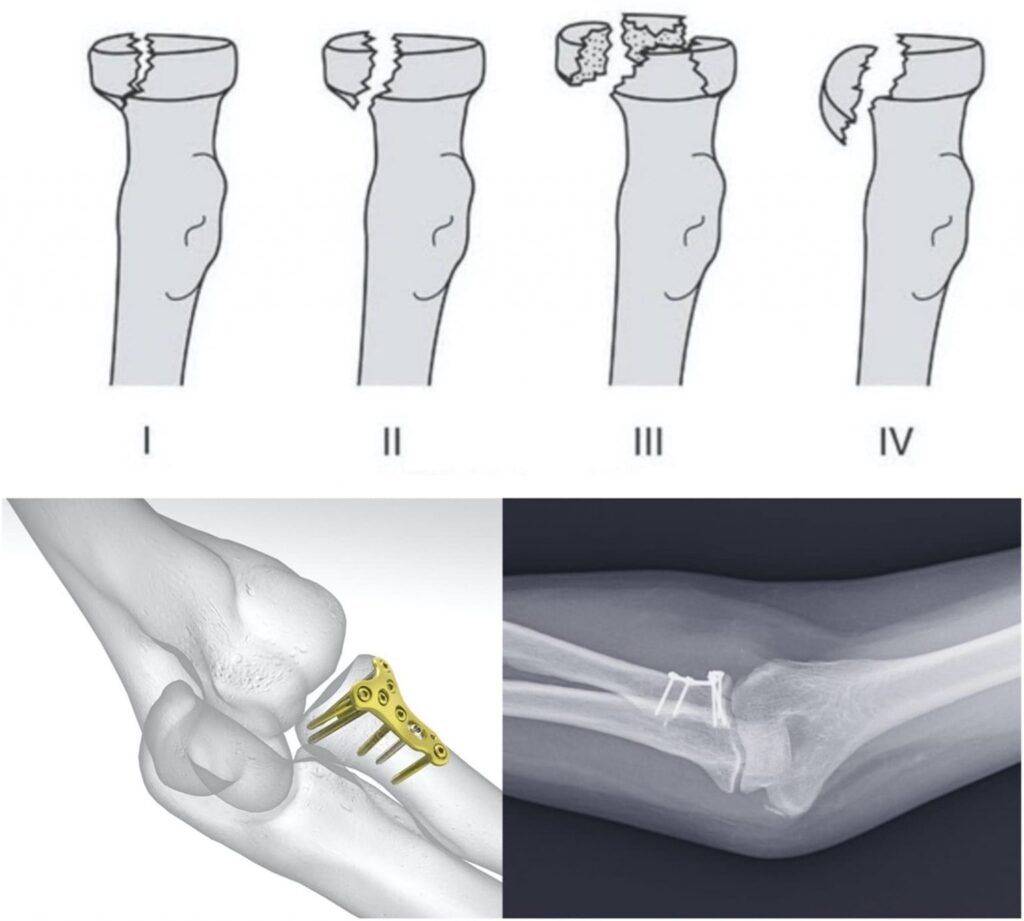

3. Κάταγμα κεφαλής κερκίδας

Συμβαίνει συνήθως σε πτώσεις με το χέρι σε έκταση. Η βαρύτητα αξιολογείται με βάση την ταξινόμηση Mason.

Αντιμετώπιση:

- Συντηρητική (σε μικρά, μη παρεκτοπισμένα κατάγματα): ακινητοποίηση 1 εβδομάδας και στη συνέχεια κινητοποίηση

- Χειρουργική (σε μεγαλύτερα ή παρεκτοπισμένα κατάγματα): σταθεροποίηση με βίδες ή πλάκες, χωρίς ανάγκη αφαίρεσης υλικών